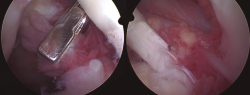

Figura 1. Imágenes en corte coronal y sagital de la ventana STIR de la RM, evidenciando rotura masiva del manguito rotador y la presencia de unas vellosidades grasas hipointensas en el seno de la bursa subacromial (señaladas mediante flechas).

En la resonancia magnética (RM) de los hombros, los citados cambios degenerativos con ­quistes subcondrales en la cabeza humeral y presencia de cambios inflamatorios en cabeza y troquíter eran evidentes, observándose el LA como una infiltración grasa con vellosidades en la cavidad articular hiperintensas en T1 y T2, con imágenes hipointensas en las ventanas STIR y supresión grasa. También se observó el acúmulo de líquido en la zona de la bursa subacromial (Figura 1), presentando en ocasiones una discreta migración proximal de la cabeza humeral. En ocasiones se evidenció también una alteración de la señal en los tendones del manguito rotador, compatibles en algún caso con roturas. En la RM de los casos de rodilla se evidenció el LA como un crecimiento de partes blandas en la bursa suprapatelar de intensidad compatible con la grasa, asociada a la presencia de derrame articular (Figura 2). Dicha masa era heterogénea, irregular, adherida al plano anterior.